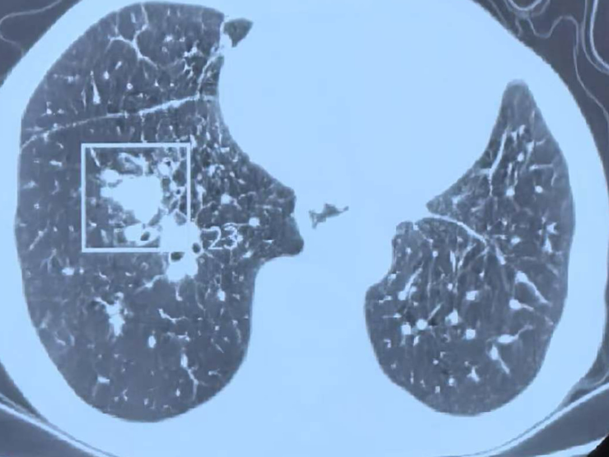

据悉,该男性患者肿瘤病史错综复杂且极为危重。此前,他先后被确诊患有喉癌、食管癌,在历经手术治疗后,又不幸罹患淋巴瘤。不仅如此,右肺还出现多发转移病灶,虽接受过肺部消融治疗且效果良好,但此次复查却如同一记重击——右肺下叶血管池内出现一处食管癌肺转移灶,最大直径达2.1厘米。

手术难度同样不容小觑。病灶位于右肺下叶血管池内,周围血管密布,犹如一张错综复杂的血管网络,且紧邻支气管,稍有不慎,穿刺过程就可能引发大出血,消融时也极易损伤气道,这无疑属于高风险禁区级操作,对手术团队的技术和经验都是极大的考验。